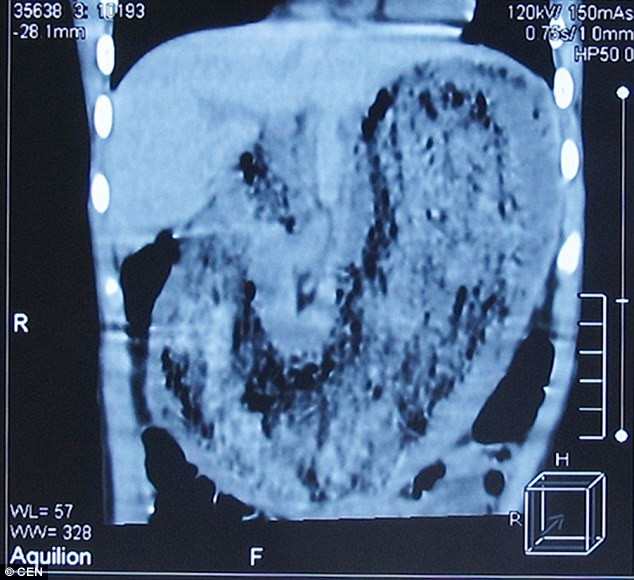

Sık sık hastalanan ve kilo kaybeden küçük kıza teşhis koyan doktor, bir fizik muayenesinin ardından çocuğun karnında bir şişlik fark etti ve yaptığı tarama sonrası, çocuğun midesinde bir nesne olduğunu ultrasonla ailesine gösterdi, fakat bu nesnenin tam olarak ne olduğu ultrasonda çok da açıkça belli değildi.

Ameliyata alınan küçük kızın midesinden tam 2 kiloluk bir bir tüy yumağı çıktı; bu saç yumağının içerisinde giysi lifleri-tüyleri ve garip hurda parçaları da çıktı.

Çok sıkı ve sert bir 'kist' şeklinde toplanan kıl yumağının, küçük kızın midesinin tam şeklini aldığı, mideyi tıkadığı için de midenin hiç bir yiyeceği kabul etmediği ve küçük kızın bu yüzden zayıf düştüğü ortaya çıktı: